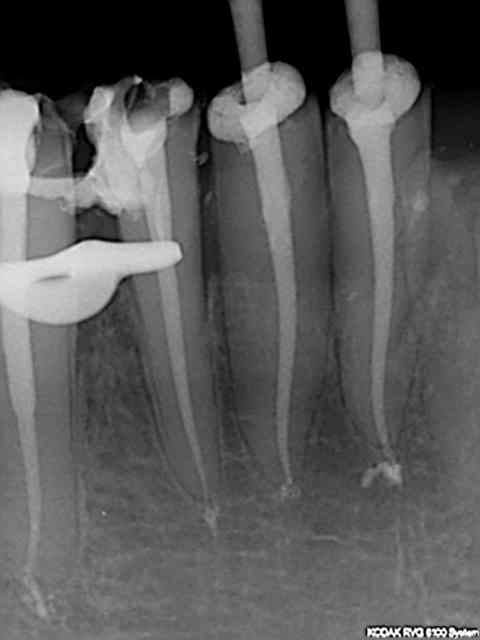

Non, en fait j'en fais une 50 aine par mois, un peu plus de 2 par jour.

En général la rapidité d'un acte dépend du nombre d'instruments rotatifs en fonction, ça évite de perdre un temps fou en changeant les fraises et les limes, et bien évidemment d'une assistante au fauteuil bien rodée (cf le post 15 mn endo molaire). Je n'ai pas l'assistante au fauteuil dommage !)

Je ne fais pas le topo sur la cavité d'accès que j'ai cependant tendance à faire bien large pour accéder aux entrées canalaires facilement.

A partir de là tous les instruments d'endo sont au préalable en place sur un instrument rotatif. Sx protaper sur l'entran, largo numéro 3 sur double bague verte, s1 protaper sur endomaster, r25 réciproc sur wd silver, SAF (pas tout le temps vu les 50 euros de l'instrument jetable) Endo activator ou rinsendo plutôt ngap oblige !)

Je fais la recherche des canaux avec l'entran et le sx que j'essaye de faire progresser le plus possible en direction apicale (sans forcer comme un bourrin, hein !) puis ouverture au largo de l'entrée canalaire et re-sx pour progresser encore jusquà environ entre 15 et 20 mm de lt (dépend de la longueur estimée de la racine à la radio pré op et de sa perméabilité). Ensuite passage du s1 avec l'endomaster qui en général descend à la lt sans problème (réglage de l'endomaster à -0.5mm lt).Stop sur le r25 qui descend sans problème à la lt. Irrigation tout au long de la procédure évidemment (sauf s1 car la lt ne peut pas etre déterminée avec l'endomaster si trop de dakin). Récapitulation si problème à l'une des étapes mais c'est rare.

Radio cone 25 en place etc....)))) j'avoue je pèche dans le etc !)))

"Le" gros plus ces derniers mois a été l'apparition du r25 réciproc qui a permis de supprimer les s2,f1, f2 protaper et ce sans casse ni fausse route à ce jour ! une révolution en rupture de stock en ce moment.))))

Mise en forme entre 2 et 5 mn par canal.